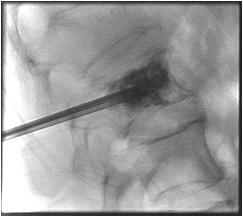

患者俯臥於X光透視檢查台上,醫師利用X光透視導引,在皮膚上施打局部麻藥後,精確的將穿刺針插入脊椎體中,再注入骨泥,注入骨泥時,醫師會一直用透視X光觀察骨泥的流動情形,以避免骨泥流入危險區域。骨泥施打完畢後,等待數分鐘,骨泥完全固化後,將穿刺針取出,傷口紗布覆蓋包紮後即完成治療。

顯示注射骨泥後的X光片。執行這項治療大約有1%~5%的風險,包括感染、出血及神經受損等。本部配備有先進的雙向X光機,可提高執行治療時的安全性 |